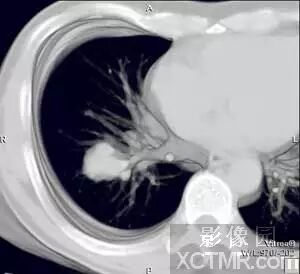

IVR图象显示支气管与肺部肿瘤之间的关系,此病例虽然没有进行增强,

但是通过图象后处理仍然清晰地 显示出肺内支气管及肿瘤组织,并且可以看到肿瘤支气管关系密切。